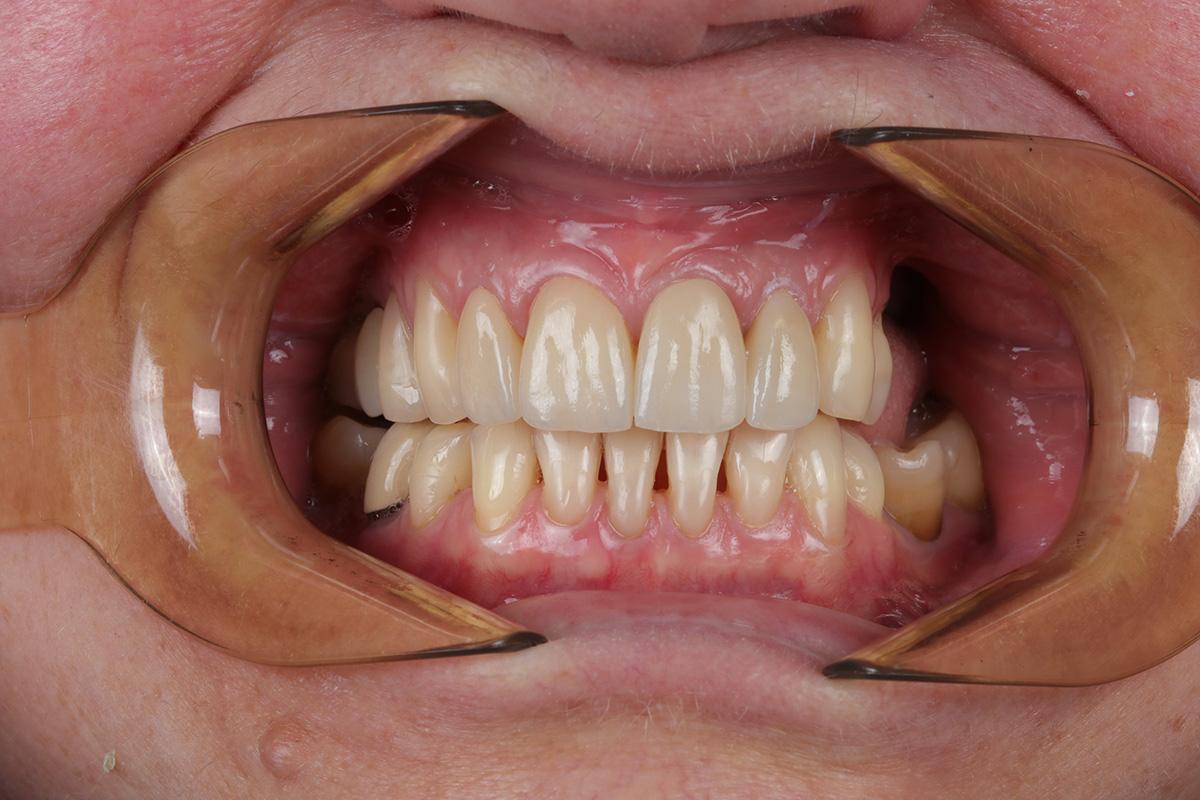

Pacjentka zgłosiła się do naszej kliniki po „uśmiech jak z Hollywood”.

Aby osiągnąć taki efekt, musieliśmy przeprowadzić ekstrakcję złamanej górnej jedynki i w jej miejsce jednoczasowo wszczepić implant, a następnie na pozostałe zęby wykonać licówki i korony pełnoceramiczne w najjaśniejszym odcieniu.

Całość została zaprojektowana w harmonii z twarzą i rodzajem uśmiechu naszej Pacjentki. Leczenie trwało 3 miesiące.

Wykonał je lek.stom. Michał Badowski we współpracy z laboratorium Dentalscan (tech.dent. Joanna Gancarz).